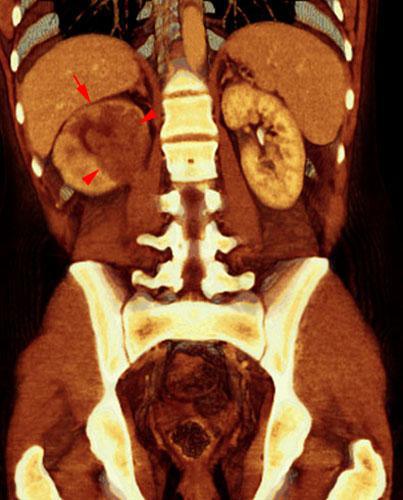

Carcinoma medular renal

VR seccional. Visión coronal anterior. Infiltración tumoral del seno renal (puntas de flecha). Disminución de la contrastación cortical (flecha) indicando infiltración vascular